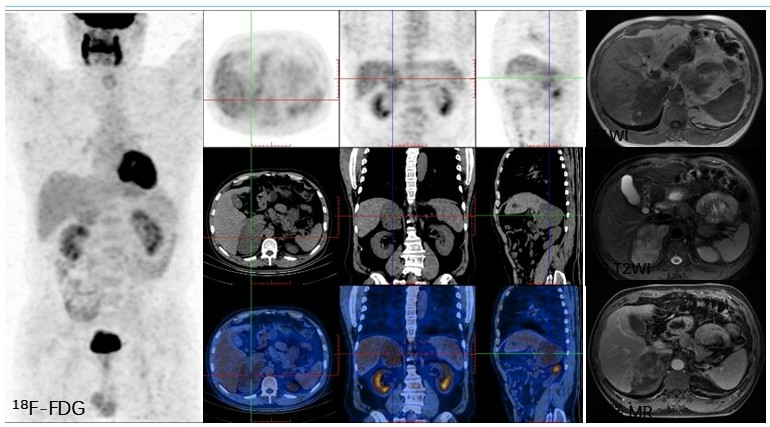

病例(8为一老年女性,间断头晕、心慌检查发现左肾上腺占位,测血压明显升高;实验室检查示ACTH水平稍低、皮质醇水平正常;增强MRI示肾上腺占位呈T1WIT2WI高低混杂信号、DWI轻度高信号,增强扫描示肿物边缘呈不均匀明显强化18F-FDG PET/CT示占位边缘区域代谢轻度增高,68Ga-奥曲肽显像中未见SSTR高表达;(左肾上腺肿物)切除病理为肾上腺皮质腺瘤。

8. 61岁,间断头晕6年,心慌3年,发现左肾上腺占位半月肾上腺皮质腺瘤